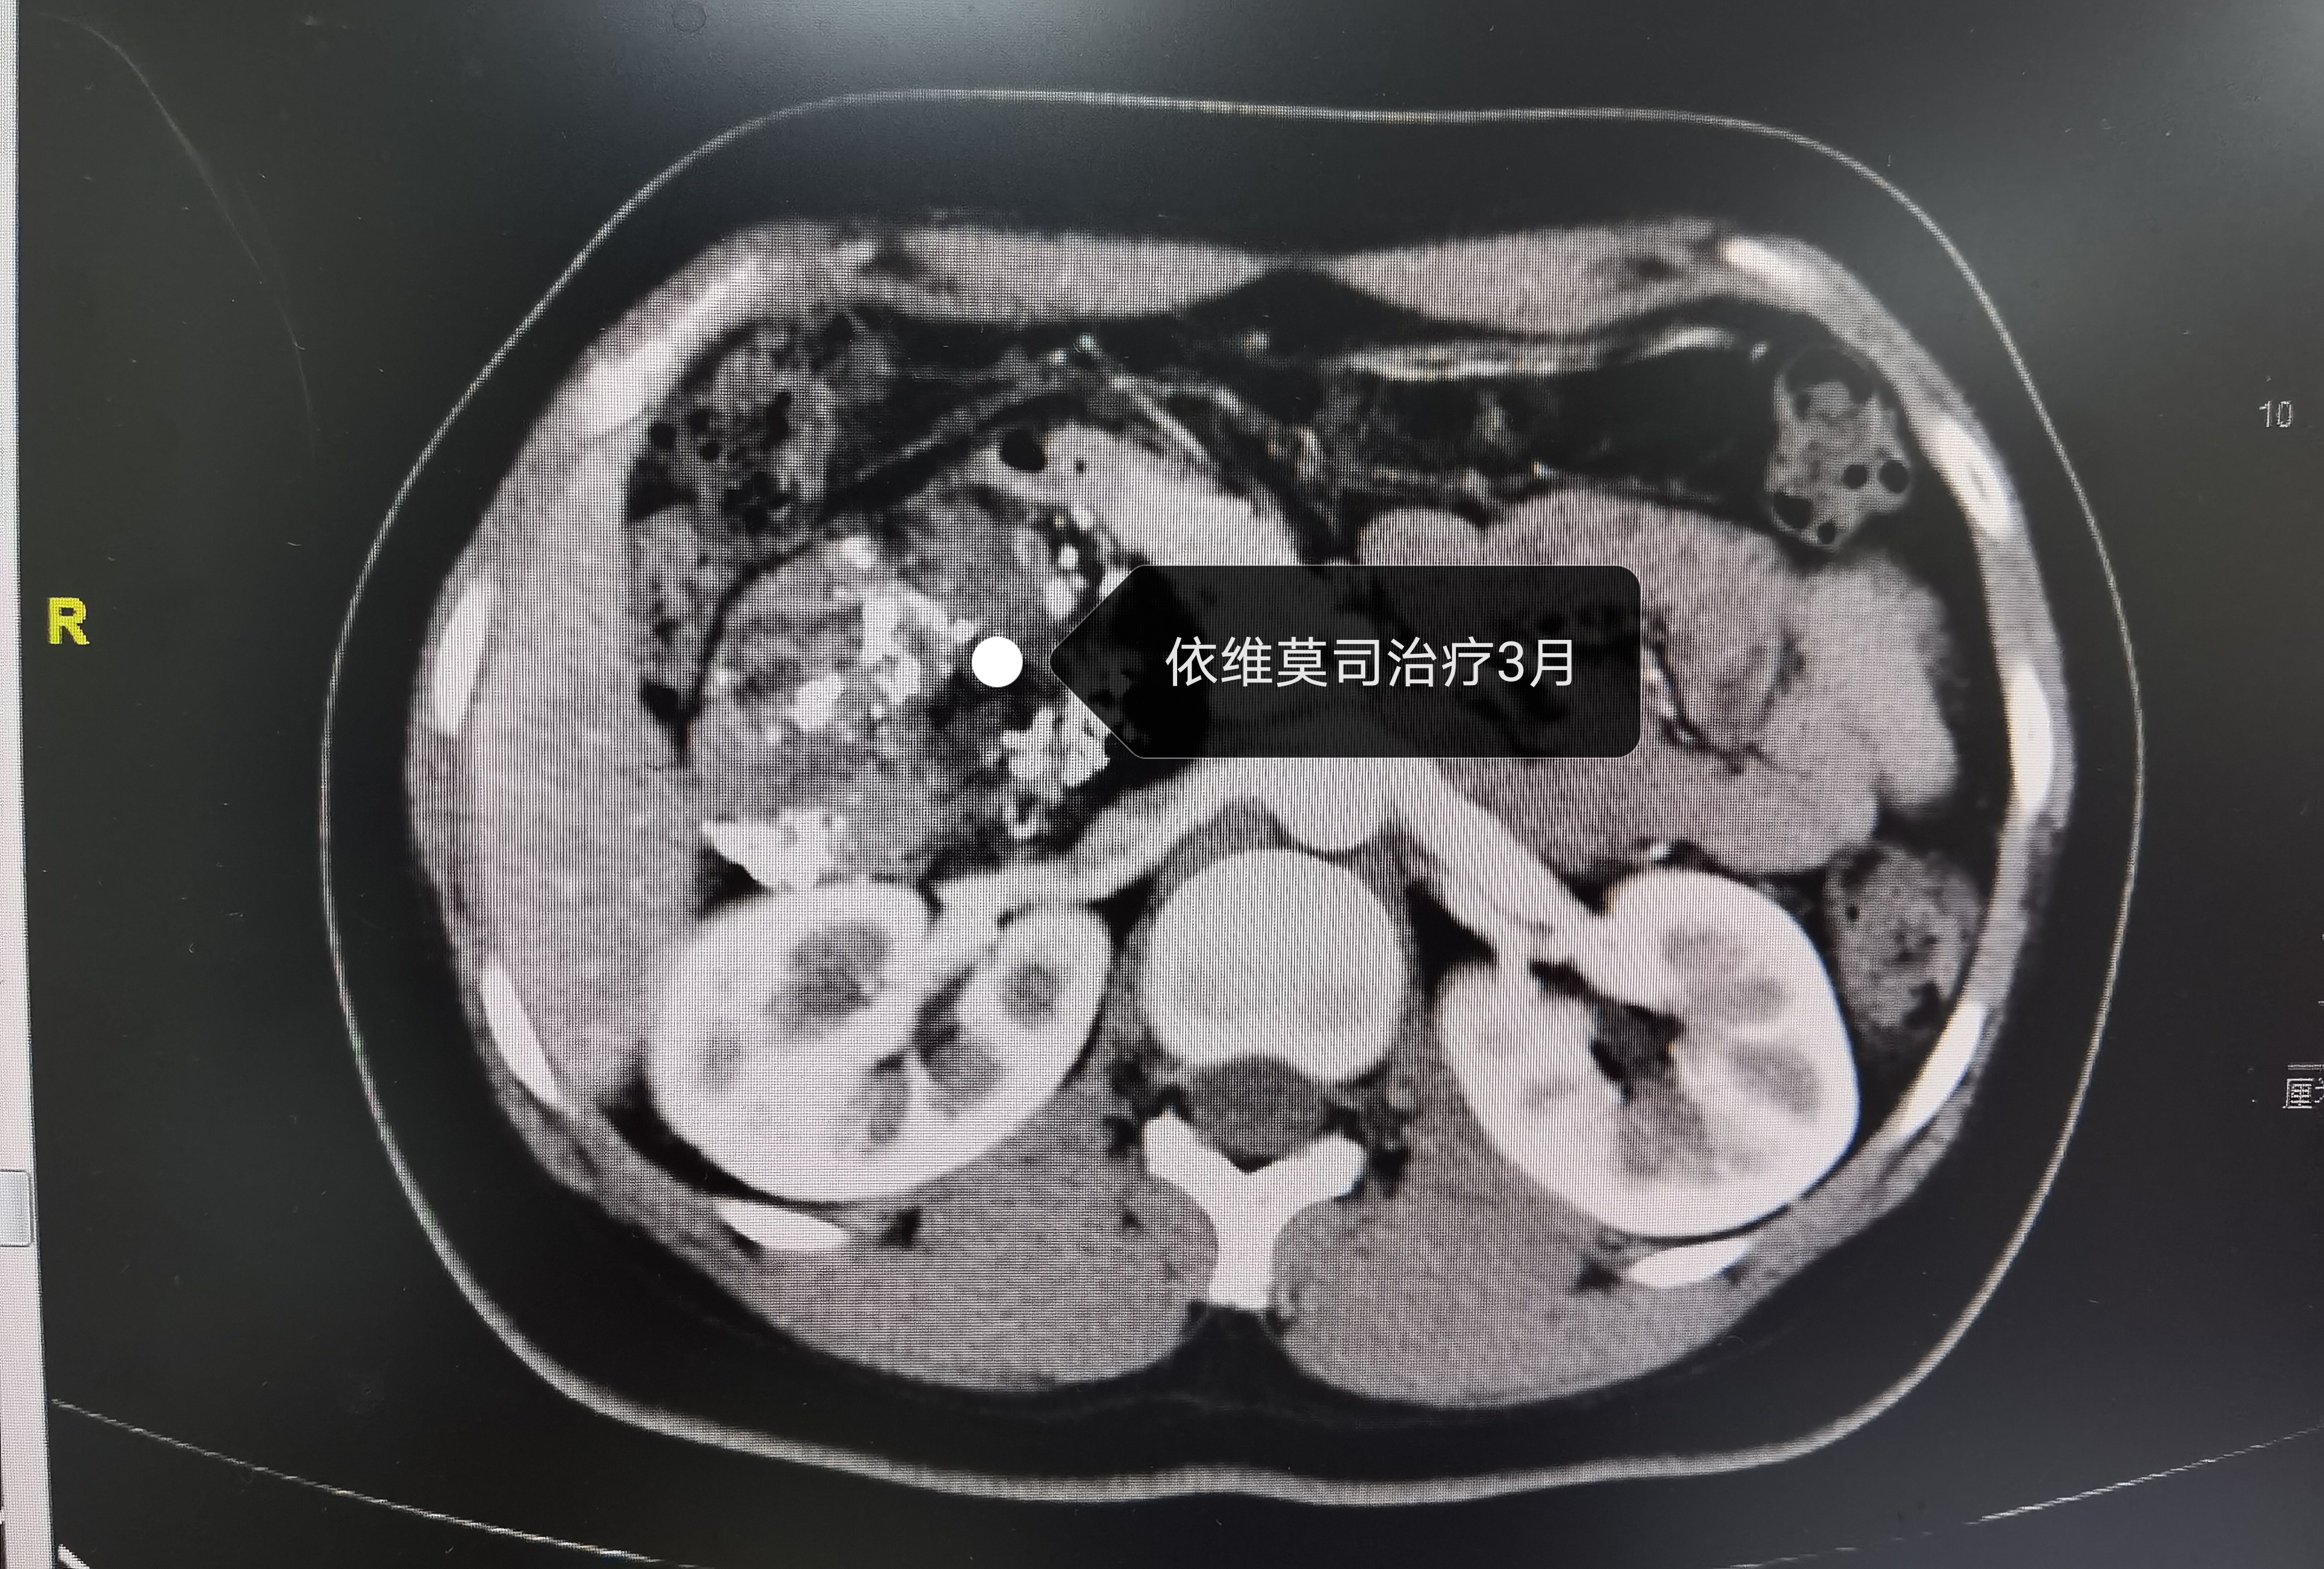

针对该情况,从2月份开始,经过我院MDT团队三次会诊,讨论了多种方案后,患者也同意了我们的方案,对我们寄予了厚望。过程很漫长,患者的依从性也是非常好,得到的结果更是喜人,会诊后我们对患者进行了介入科两次动脉栓塞,依维莫司治疗三个月,肿瘤较之前显著缩小。终于在今日(2020年 12月3日)进行了手术。

依维莫司治疗三个月